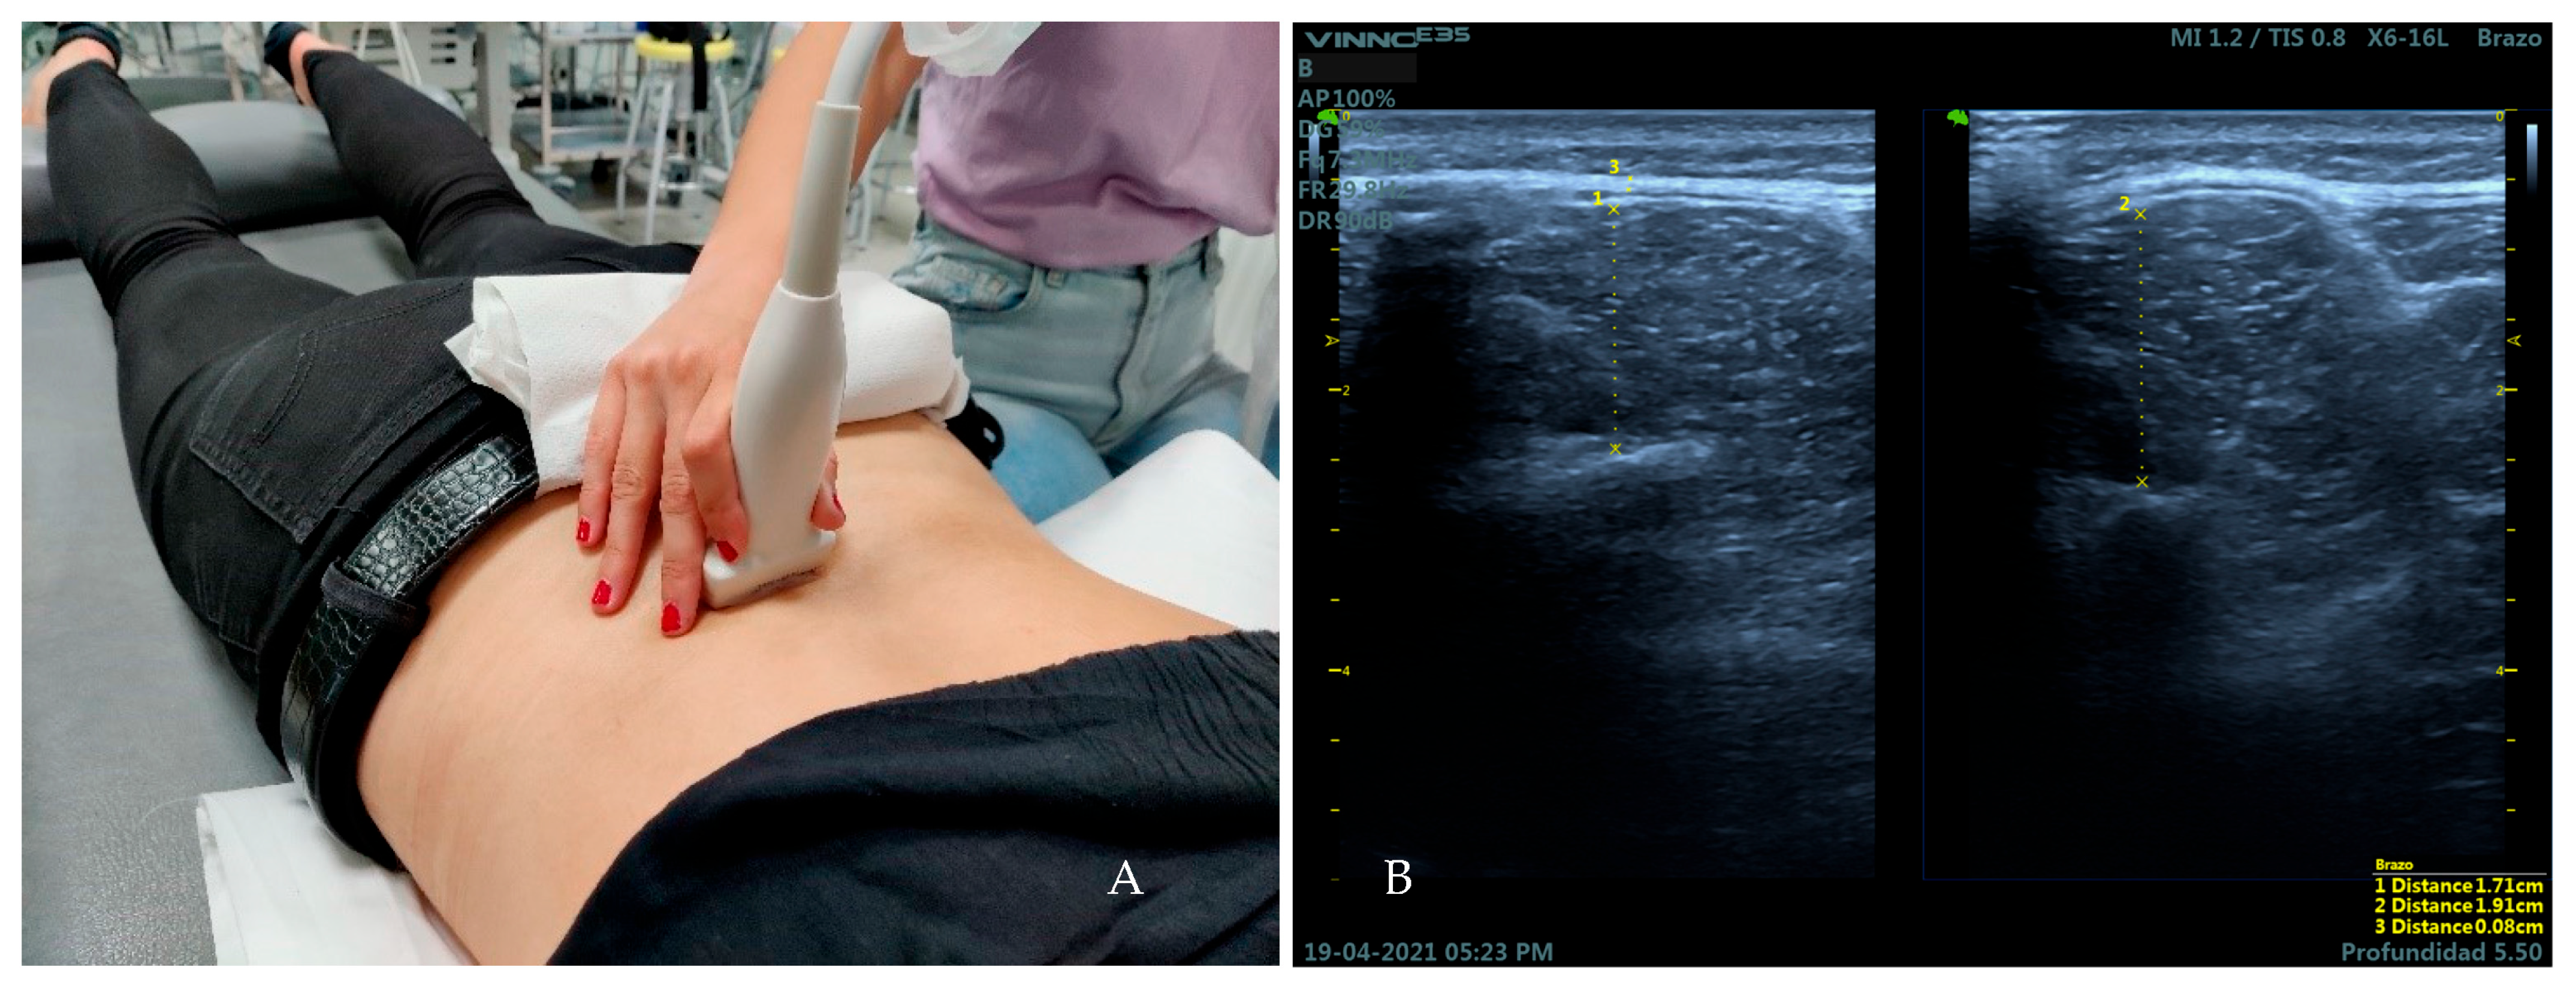

2.5. Measures